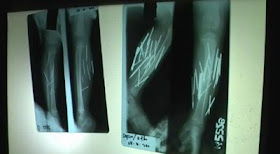

အင္ဒိုနီးရွားႏုိင္ငံ၊ ဆူလာေ၀ဆီေတာင္ပိုင္း၊ ပရီပါရီ ျမိဳ႕က ၃ ႏွစ္အရြယ္ မိန္းကေလး ဆာဖီရာ မွာေတာ့ ထူးထူးဆန္းဆန္း ဂမၻီရဆန္ဆန္အျဖစ္အပ်က္ကေလး ျဖစ္သြားပါတယ္။  ဒါကေတာ့ သူမေျခေထာက္ထဲကို သံႏွင့္ အပ္ကဲ့သို႕ေသာ သတၱဳေခ်ာင္းမ်ား စိုက္၀င္ေနျခင္းပါ။  ဒီမတုိင္ခင္ လအနည္းငယ္ကထည္းက ဒီမိန္းကေလးဟာ သူမေျခေထာက္ေတြ နာက်င္ေနတယ္လို႕ သူမမိခင္ကို ေျပာပါတယ္တဲ့။  ေနာက္ဆံုးေတာ့ သူမမိခင္လည္း မိန္းကေလးကို ေဆးရံုကို ေခၚသြားျပီး ျပပါတယ္။  ဆရာ၀န္ေတြ ဓာတ္မွန္ရိုက္ၾကည့္လိုက္တဲ့ အခါမွာေတာ့ သံေတြ၊ အပ္ေတြလို အရာ၀တၱဳေတြဟာ ကေလးမရဲ႕ ေျခေထာက္ထဲမွာ နစ္ျမဳတ္ေနတာကို ေတြ႕ရွိရပါသတဲ့။

ဒီ သံေခ်ာင္းေတြ၊ အပ္ေတြ ဖယ္ထုတ္ဖို႕ ခြဲစိတ္တာ ၂ နာရီေလာက္ၾကာပါတယ္။

မိန္းကေလးရဲ႕ ေျခေထာက္ထဲကို သံေခ်ာင္းေပါင္း ၂၇ ေခ်ာင္းစိုက္၀င္ေနတာျဖစ္ျပီး ၂၆ ေခ်ာင္းကို ေအာင္ျမင္စြာ ဖယ္ထုတ္ႏုိင္ခဲ့ပါတယ္။  ဒါေပမယ့္ က်န္တဲ့ သူ႕မရဲ႕ ေျခေထာက္ေနာက္ဖက္ကို စိုက္၀င္ေနတဲ့ တစ္ေခ်ာင္းကေတာ့ ဖယ္ထုတ္ဖို႕  မလြယ္လွပါဘူး။  ဘာျဖစ္လို႕လဲဆိုေတာ့ အာရံုေၾကာေတြ ဆံုေနတဲ့ အဓိကေနရာျဖစ္ေနတာေၾကာင့္ ဒါကို ဖယ္ထုတ္ဖို႕ အထူးဂရုစိုက္ရမယ္လို႕ ဆိုပါတယ္။